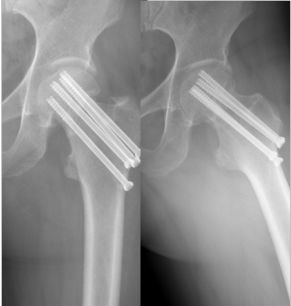

补救:取下一枚钉子骨折愈合了,关键是取钉子后减少了应力集中,延长了钢板的寿命,骨折愈合了。如果骨不愈合钢板迟早断裂(钢板当初放在内侧会好,蝶形骨块不会坏死,腓骨固定后外侧稳定,内外柱均衡愈合机会增加,当然最好还是髓内钉)。

取下3枚钉子骨折愈合了,与上一例同一位医生所做。张力带钢板,去除3螺钉后,钢板的应力分散,弹性增加,骨折端承受有效的应力刺激,最后骨折愈合。去除螺钉的时候如果加骨皮质剥离重新激发骨愈合会更好。(最好选髓内钉)